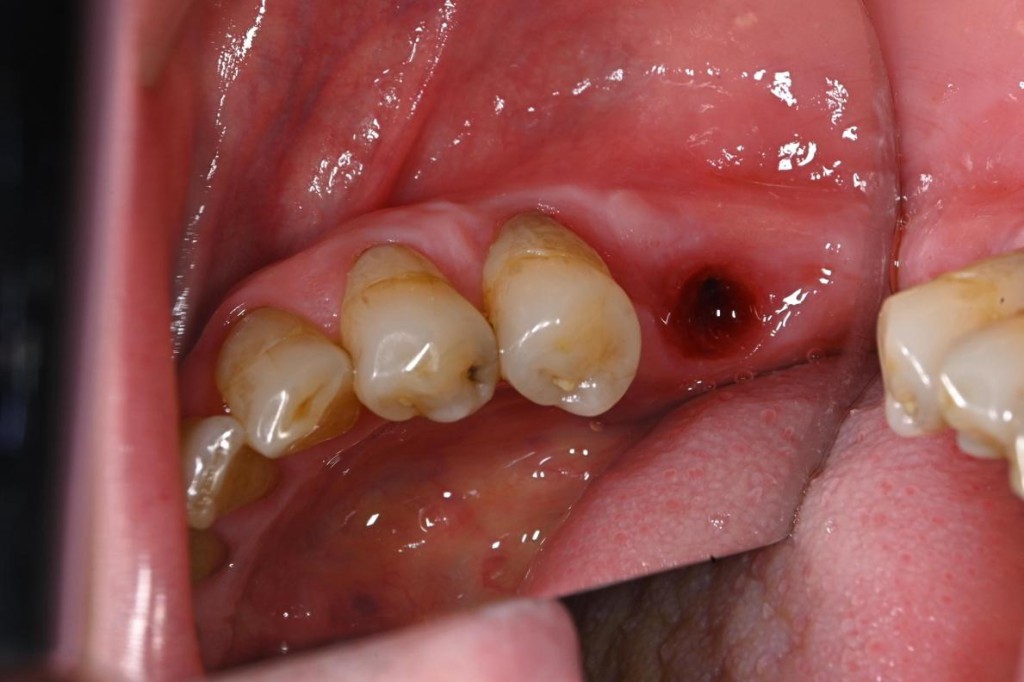

【治療前】

| 治療内容 | 下顎奥歯のインプラント治療 |

| 治療期間 | 2ヶ月 |

| 治療費用 | 31万円( 税抜 ) |

| 副作用・リスク | 外科処置が伴うため、術後の疼痛・腫脹・出血・咬合痛などを生じる事があります。 麻酔を行う場合、腫れやむくみを生じる事があります。 また、被せ物や土台が外れたり、欠けたり、緩んだりする事があります。 |